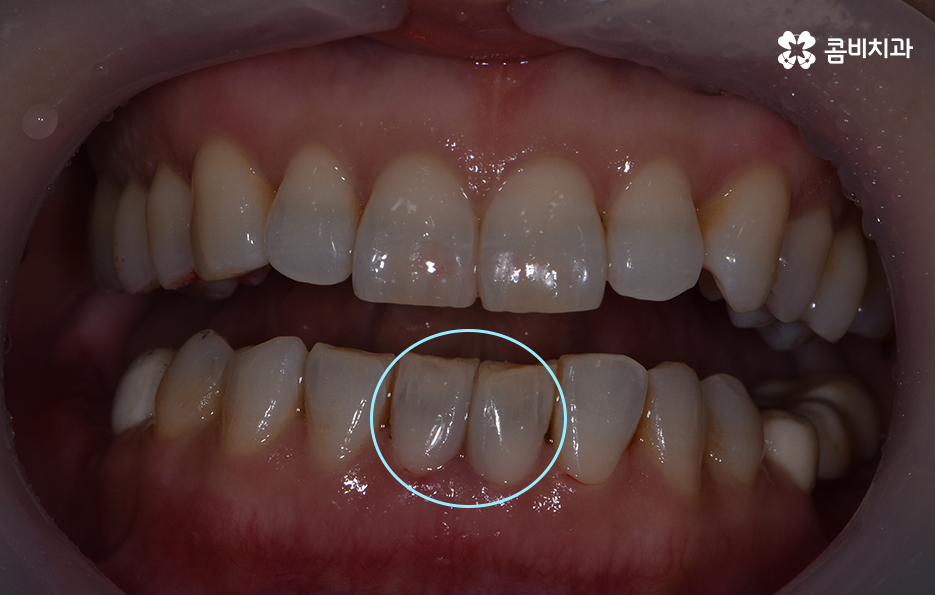

위 환자분의 경우 블랙트라이앵글 레진으로 치료를 하였는데

이러한 레진 치료의 장점은 빠르게 심미성을

회복할 수 있다는 점이며 비교적 저렴하다는 장점이 있습니다.

치아 사이에 발생한 블랙트라이앵글은 미관상 좋지 않기 때문에

심미 치료를 위해 공간을 채우는 방법이나 벌어진 치아 사이를

교정하는 방법으로 보통 치료가 진행이 됩니다.